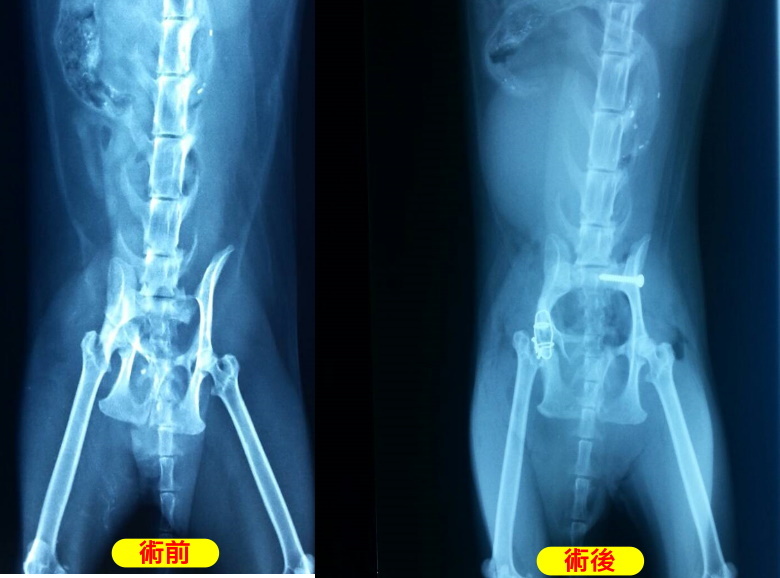

主題: 被肇逃的車禍虎斑吉妹 申請者姓名: 埋愛葬心 花色: 申請日期: 2014-06-01 01:47:19 申請者部落格: 申請者臉書網址: 所在縣市/合作醫院: 桃園縣/陳獸醫院 治療費用: 21900元 需求人數: 24人 已結案 (2014-07-02 17:30:00) 報名人員: 蘇小吉(已付款)、ERic YU(已付款)、Yun Shan(已付款)、點兒(已付款)、Cindy Hung、Cindy Hung(已付款)、王衣若(已付款)、尖頭怪(已付款)、Bonnie Lee(已付款)、Ou Han(已付款)、可樂兒(已付款)、曹立松(已付款)、松鼠(已付款)、Lucia Lin(已付款)、李毓華(已付款)、陳珍妮(已付款)、Sunny Chen(已付款)、Shizuka Ho(已付款)、mavis(已付款)、JasmineC(已付款)、Po-Lin Chen(已付款)、老皮(已付款)、吳毓軒(已付款)、Kith Shiu(已付款)、小四(已付款)、 候補人員: 動物病情說明: 103/05/06-雨天

到院後 果然嚴重骨折